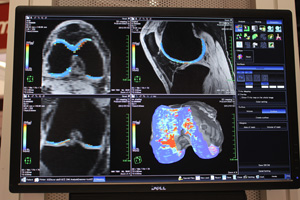

●3D Mapping

3D Mapping

3D Mappingは,軟骨の組織性状を評価し,変性の程度を定量化するソフトウェア。軟骨の組織は規則的な配列となっているが,リウマチなどにより変性が起こると,その規則性に変化が生じる。T1ρマップやT2マップにより,軟骨内の水やコラーゲン,グルコサミノグリカンを定量化し,三次元表示した軟骨にカラーマッピングを行う。異常組織を赤,正常組織を青で表示し,一目で変性の程度を把握できるため,検出やフォローに活用できる。膝の関節症は非可逆的な変化のため,早期発見・早期治療により,進行を止めることが重要となる。継続的なフォローが必要なため,被ばくのないMRIを用いることで,QOL維持に貢献する。

●Wash-out Map(FDA未申請)

Wash-out Map

Wash-out Mapは,腫瘍を造影して信号値が上がったあとに,どの程度wash-outするかを評価する機能で,従来のダイナミック造影解析ソフトウェアに搭載される。悪性のしきい値はピークからは−20%と規定されているが,評価結果を視覚化することで,腫瘍のどの位置が悪性度が高いと想定されるかが明瞭になり,生検における悪性度の高い部分の採取を支援する。

4D Flow AnalysisとWash-out Map